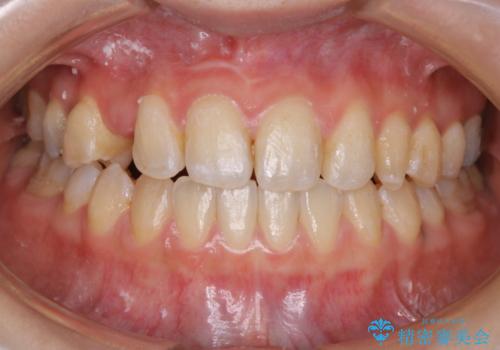

- 受け口で、前歯の嚙み合わせが気になるとの事でご相談にいらした方です。先天的に右上犬歯がなく、左上犬歯も小さい状態でした。矯正治療にて周囲の歯を動かして歯のスペースを確保した上で、被せものにて歯を作っていきました。

歯科技工士さんの熟練した技術により、周囲の歯としっかりなじむ天然歯のような被せ物をお作りすることが出来ました。

矯正治療と補綴治療をうまく組み合わせることで、美しい口元に仕上げることが出来ました。矯正治療、補綴治療をまとめて行える総合歯科治療を体現した治療といえます。